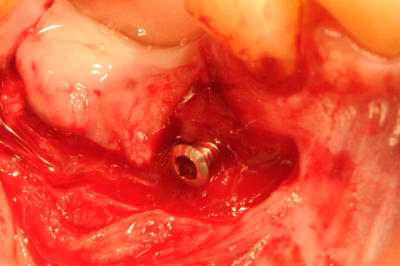

photo 6-7-8 : retrait des vis FAST ayant servi de piquet de tente à la ROG

Sur la photo vis en place : elle est déjà un peu dévissée, ou il y a eu 2 mm de perte du matériaux ? ( c'est ce que j'ai eu aussi les deux fois ou j'ai fait cette technique ).

En effet si on compare la photo de ton post initial par rapport à la photo de la réouverture, on peut voir que la vis dépasse toujours autant par rapport au niveau osseux initial.

pour clio et jeff, la photo montrant la vis est trompeuse et je comprends mieux vos réactions.

en fait elle n'était pas dans sa position initiale car j'ai fait la photo avec la vis ayant été retirée à moitié.

photos 1 et 2 mise en place des vis et comblement osseux.

photo 3 et 4 le niveau osseux n'a pratiquement pas bougé.